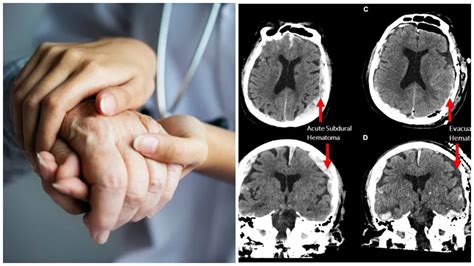

Nový výskum ukazuje, že prispôsobená verzia stredomorskej diéty, známa ako MIND diéta, je spojená so spomalenejším starnutím mozgu. Najvýraznejšie sa tento efekt prejavil u šedej hmoty - tkaniva, ktoré zabezpečuje kľúčové funkcie ako myslenie, pamäť a rozhodovanie.

Najzaujímavejším zistením štúdie je, že ľudia, ktorí dodržiavali MIND diétu, mali mozog „mladší“ v priemere o viac ako dva roky v porovnaní s tými, ktorí sa stravovali menej zdravo. Vedci sledovali účastníkov dlhodobo a analyzovali ich stravovacie návyky v spojení s vývojom mozgových funkcií.